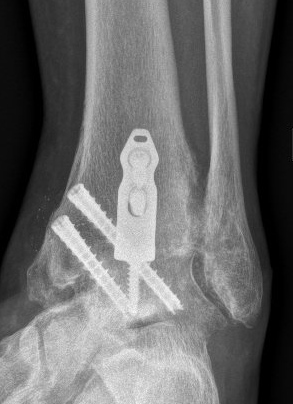

Ankle fusion is permanently stiffening the bones of the ankle together with plates and screws. This procedure is also known ankle arthrodesis.

Dr Beamond performs ankle fusion using three techniques (see images below):

- anterior open ankle fusion

Ankle replacement technology continues to develop as our understanding of why these implants fail also develops. Better design, materials and patient-specific instruments are making the current generation of implants (2015 and beyond) more reliable (see images below).